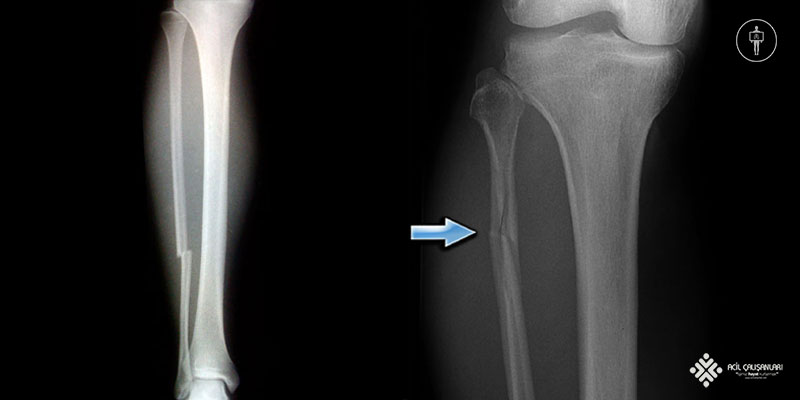

- Fibula Şaft Kırıkları: Fibula’nın orta kısmında, uzun kemik şaftında meydana gelen kırıklardır. Genellikle direkt travmalar veya burkulmalar sonucu oluşur. İzole fibula şaft kırıkları nadirdir ve genellikle tibia kırıklarıyla birlikte görülür.

İzole fibula şaft kırıkları çok nadir görülür ve genellikle bacağa doğrudan travma sonucu oluşur. Özellikle yakın zamanda bacağa doğrudan darbe almış ve fibula üzerinde palpasyonla hassasiyet bulunan bir hastada, fibula şaft kırığı düşünülmelidir. Bu tür bir durumda, fizik muayenede bacakta travma ile uyumlu olabilecek travma izi, ekimoz gibi cilt bulgularının değerlendirilmesi önem taşır. İzole fibula kırıkları nadir görüldüğünden, tüm ekstremitenin incelenmesi, özellikle o bölgenin üstündeki ve altındaki eklemlerin hareket açıklığının değerlendirilmesi gerekir.

Diz herhangi bir ligamentöz instabilite açısından kontrol edilmeli, ayak bileği ise herhangi bir yaralanma açısından dikkatle değerlendirilmelidir. Alt bacak röntgenlerine ek olarak, diz ve ayak bileğinin özel görüntülemeleri diğer kırıkları ekarte etmek açısından önemlidir. Fibula veya tibianın geri kalanında başka kırık olmaksızın fibula boynunda bir kırık tespit edilirse, bu durum sindesmotik yaralanmayı düşündürür ve “Maisonneuve kırığı” olarak adlandırılır. Benzer şekilde, ayak bileği ekleminin 15 cm yakınında bir fibula kırığı varsa, tibia kemik tutulumu, bağ yaralanması veya her ikisinin birden olması muhtemeldir.